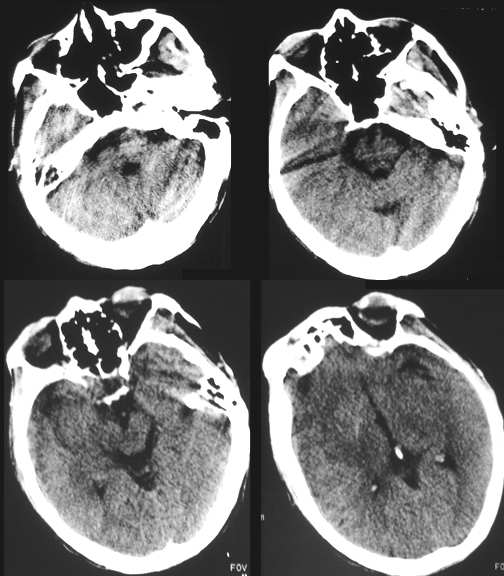

m,56,入院前不明原因的出现左恻肢体无力,无呕吐,头昏,意识障碍,查体,左恻肢体肌离1-2级,左恻提睾反射消失。

平扫。

此片我考虑是左恻基底节区脑梗塞,但我想请各位战友看看还有其它可能没有,另外右恻外恻裂池扩张怎么解释。

[emb6]右侧基底节区脑梗塞,占位效应明显(肿瘤不除外);建议跟踪复查。

支持左恻基底节区脑腔梗伴脑水肿;

右侧基底节不规则性低密度影,不强化,仔细看好象颞叶和额叶受侵,结合病史考虑:

星星细胞瘤[emb14]

左恻基底节区脑腔隙性脑梗塞伴脑水肿? 当然脑瘤不除外建议mri检查

[emb6]右侧基底节区脑梗塞。